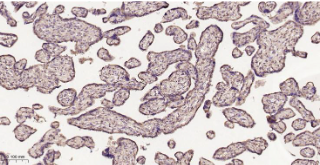

Immunohistochemical analysis of paraffin embedded Human placenta tissue slide using IHC0569H (Human LRP1 Kit).

Immunohistochemical analysis of paraffin embedded Human testis tissue slide using IHC0569H (Human LRP1 Kit).